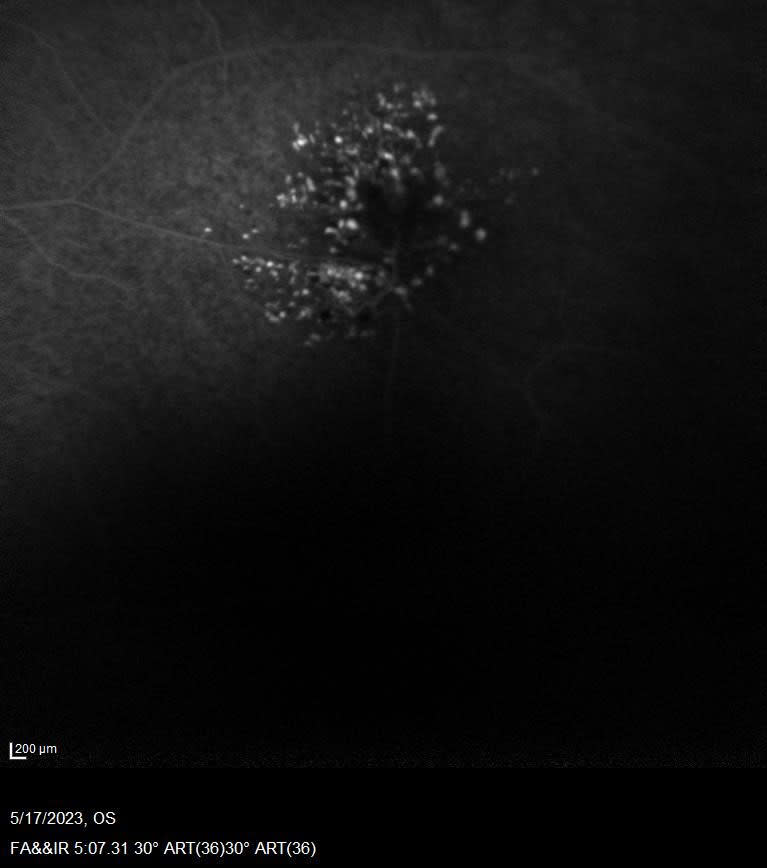

The team utilized various imaging techniques to further study these findings. Optical coherence tomography (OCT) imaging confirmed the cystic character of the lesion, revealing structurally normal overlying retinal tissue (Figure 1). Fluorescein angiography (FA) displayed hyperfluorescence with late staining, yet no signs of leakage were detected (Figure 2). After these 2 diagnostic tests, magnetic resonance imaging (MRI) of the brain was recommended to exclude any potential intracranial involvement.